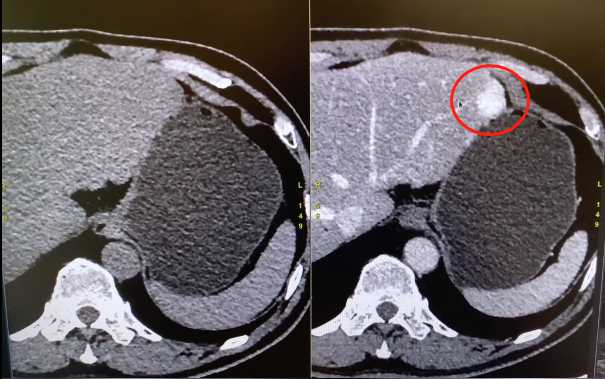

图片

▲左图是普通CT,右图是增强CT